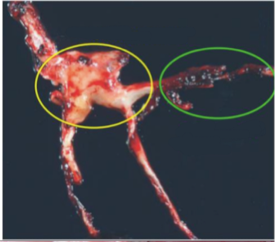

What is the area circled in yellow called? In green?

Yellow: Chicken Fat Clot

Green: Jelly Clot

How do you tell the difference between a blood clot that forms antemortem and one that forms postmortem?

Antimortem clot: Dry, friable, and attached to the lumen of the vein.

Postmortem clot: Pale in spots due to livor mortis. Clot is easily detached from and is wet and shiny.